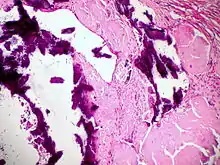

![]() Melanom-Metastase im Lymphknoten. |